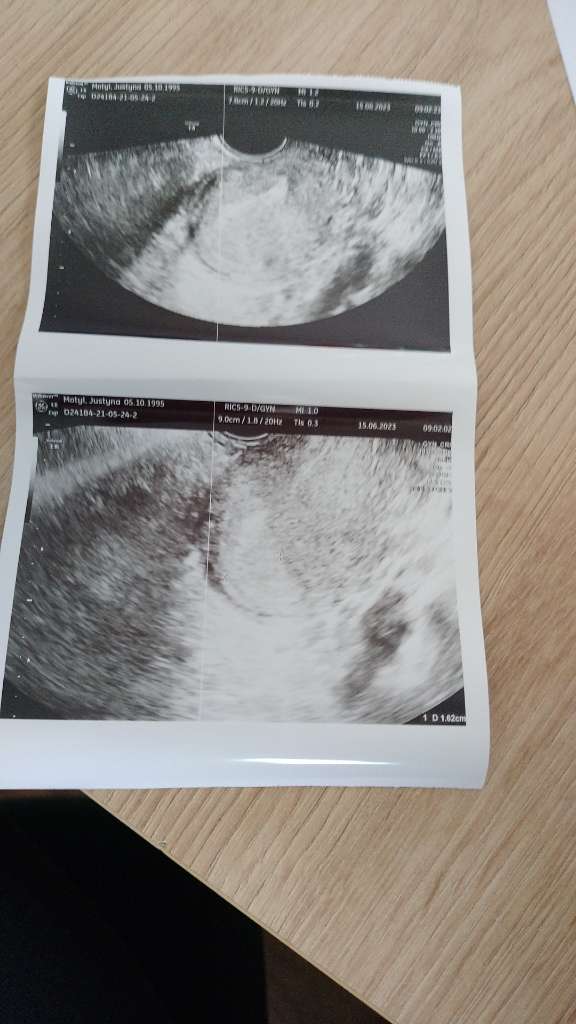

A kiedy badałaś betę i ile wynosiła? Może rzeczywiście za wcześnie by coś było widaćHej ja po wizycie i nic nie widać żadnego pęcherzyka

wczoraj była 1104 przyrost 126% w 48h .A kiedy badałaś betę i ile wynosiła? Może rzeczywiście za wcześnie by coś było widać

Hej ja po wizycie i nic nie widać żadnego pęcherzyka![]()

To przyrost bardzo ładny. Może rzeczywiście kwestia dwóch-trzech dni i się kropek pojawi. Trzymam kciukiwczoraj była 1104 przyrost 126% w 48h .

Przyrosty masz ładne , a beta na granicy, żeby zobaczyć kropka. Wszystko też zależy od sprzętu i wprawnego oka. Wiem, że się stresujesz , ale nie wszystko stracone. Tule i wierzę , że będzie dobrzeHej ja po wizycie i nic nie widać żadnego pęcherzyka![]()